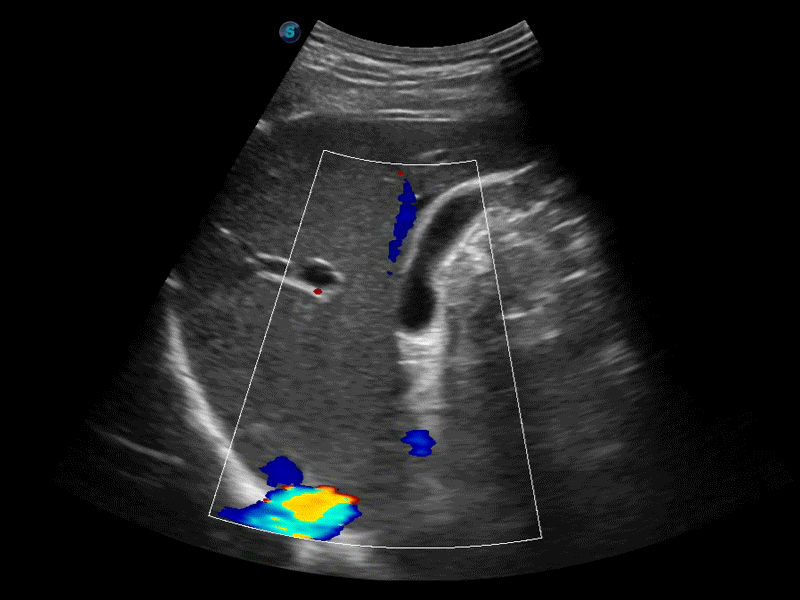

• 膀胱自动测量Auto Bladder

膀胱自动测量,一键式膀胱壁追踪和容量测量可有效提供更精确的轮廓和结果,不受膀胱形状和大小的影响。

• 血管内中膜自动测量Auto IMT

自动识别前后壁内膜厚度,为心血管疾病早期评估提供快速准确依据。